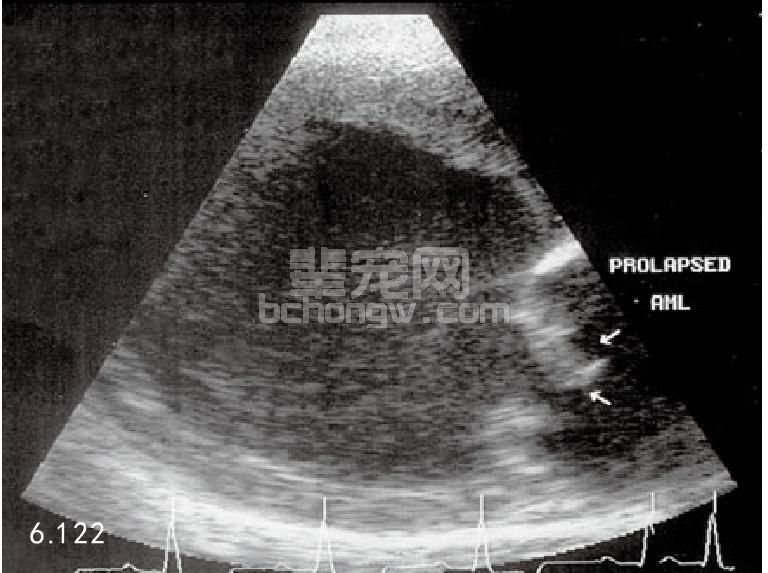

超声波心动描记术 在老龄的心内膜病病例,可确诊增厚的房室瓣小叶,以及进一步发展的左心房和左心室 扩张。除非随后发生心肌衰竭,否则左心室将出现伴有增加部分缩短的运动功能亢进。在严重的病例中,可能 有房室瓣叶垂脱到左心房。如果腱断裂,就会发生房室瓣叶杂乱无章的震颤。多普勒超声波心动描记术可确诊 心缩时心脏口回流反射进入左心房(图6.121~图6.123)。

图6.121和图6.122 1岁骑士查理王猎犬的超声波心动描记,该犬患心内膜病且二尖瓣下垂入左心房。